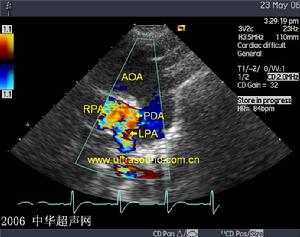

5、彩色多譜勒超聲心動圖:右心室增大,確定狹窄的解剖學位置及程度。

5、超聲心動圖可顯示瓣膜活動及狹窄情況,有無漏斗部肌型梗阻。

6、心導管檢查可測定右心室壓力是否顯著高於肺動脈壓力,並連續描記肺動脈至右心室壓力曲線;鑑別狹窄的類型(瓣膜型或漏斗型);測定心腔和大血管血氧含量;注意有無其他先天性異常。疑為漏斗部狹窄或法洛三聯症者,可行右心導管造影。